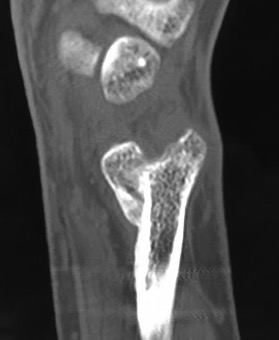

Suav-Kapanji

Technique

- distal radio-ulna arthrodesis with distal ulna pseuodoarthrosis

- distal ulna fused to distal radius with 2 screws

- distal ulna stabilised with half FCU

- interposition with pronator quadratus